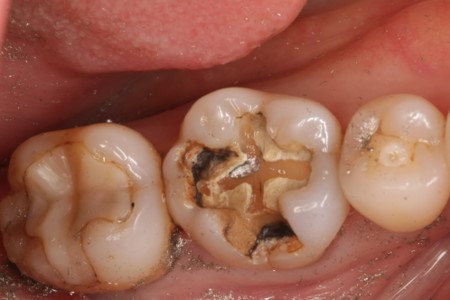

• 治療前

• 治療後